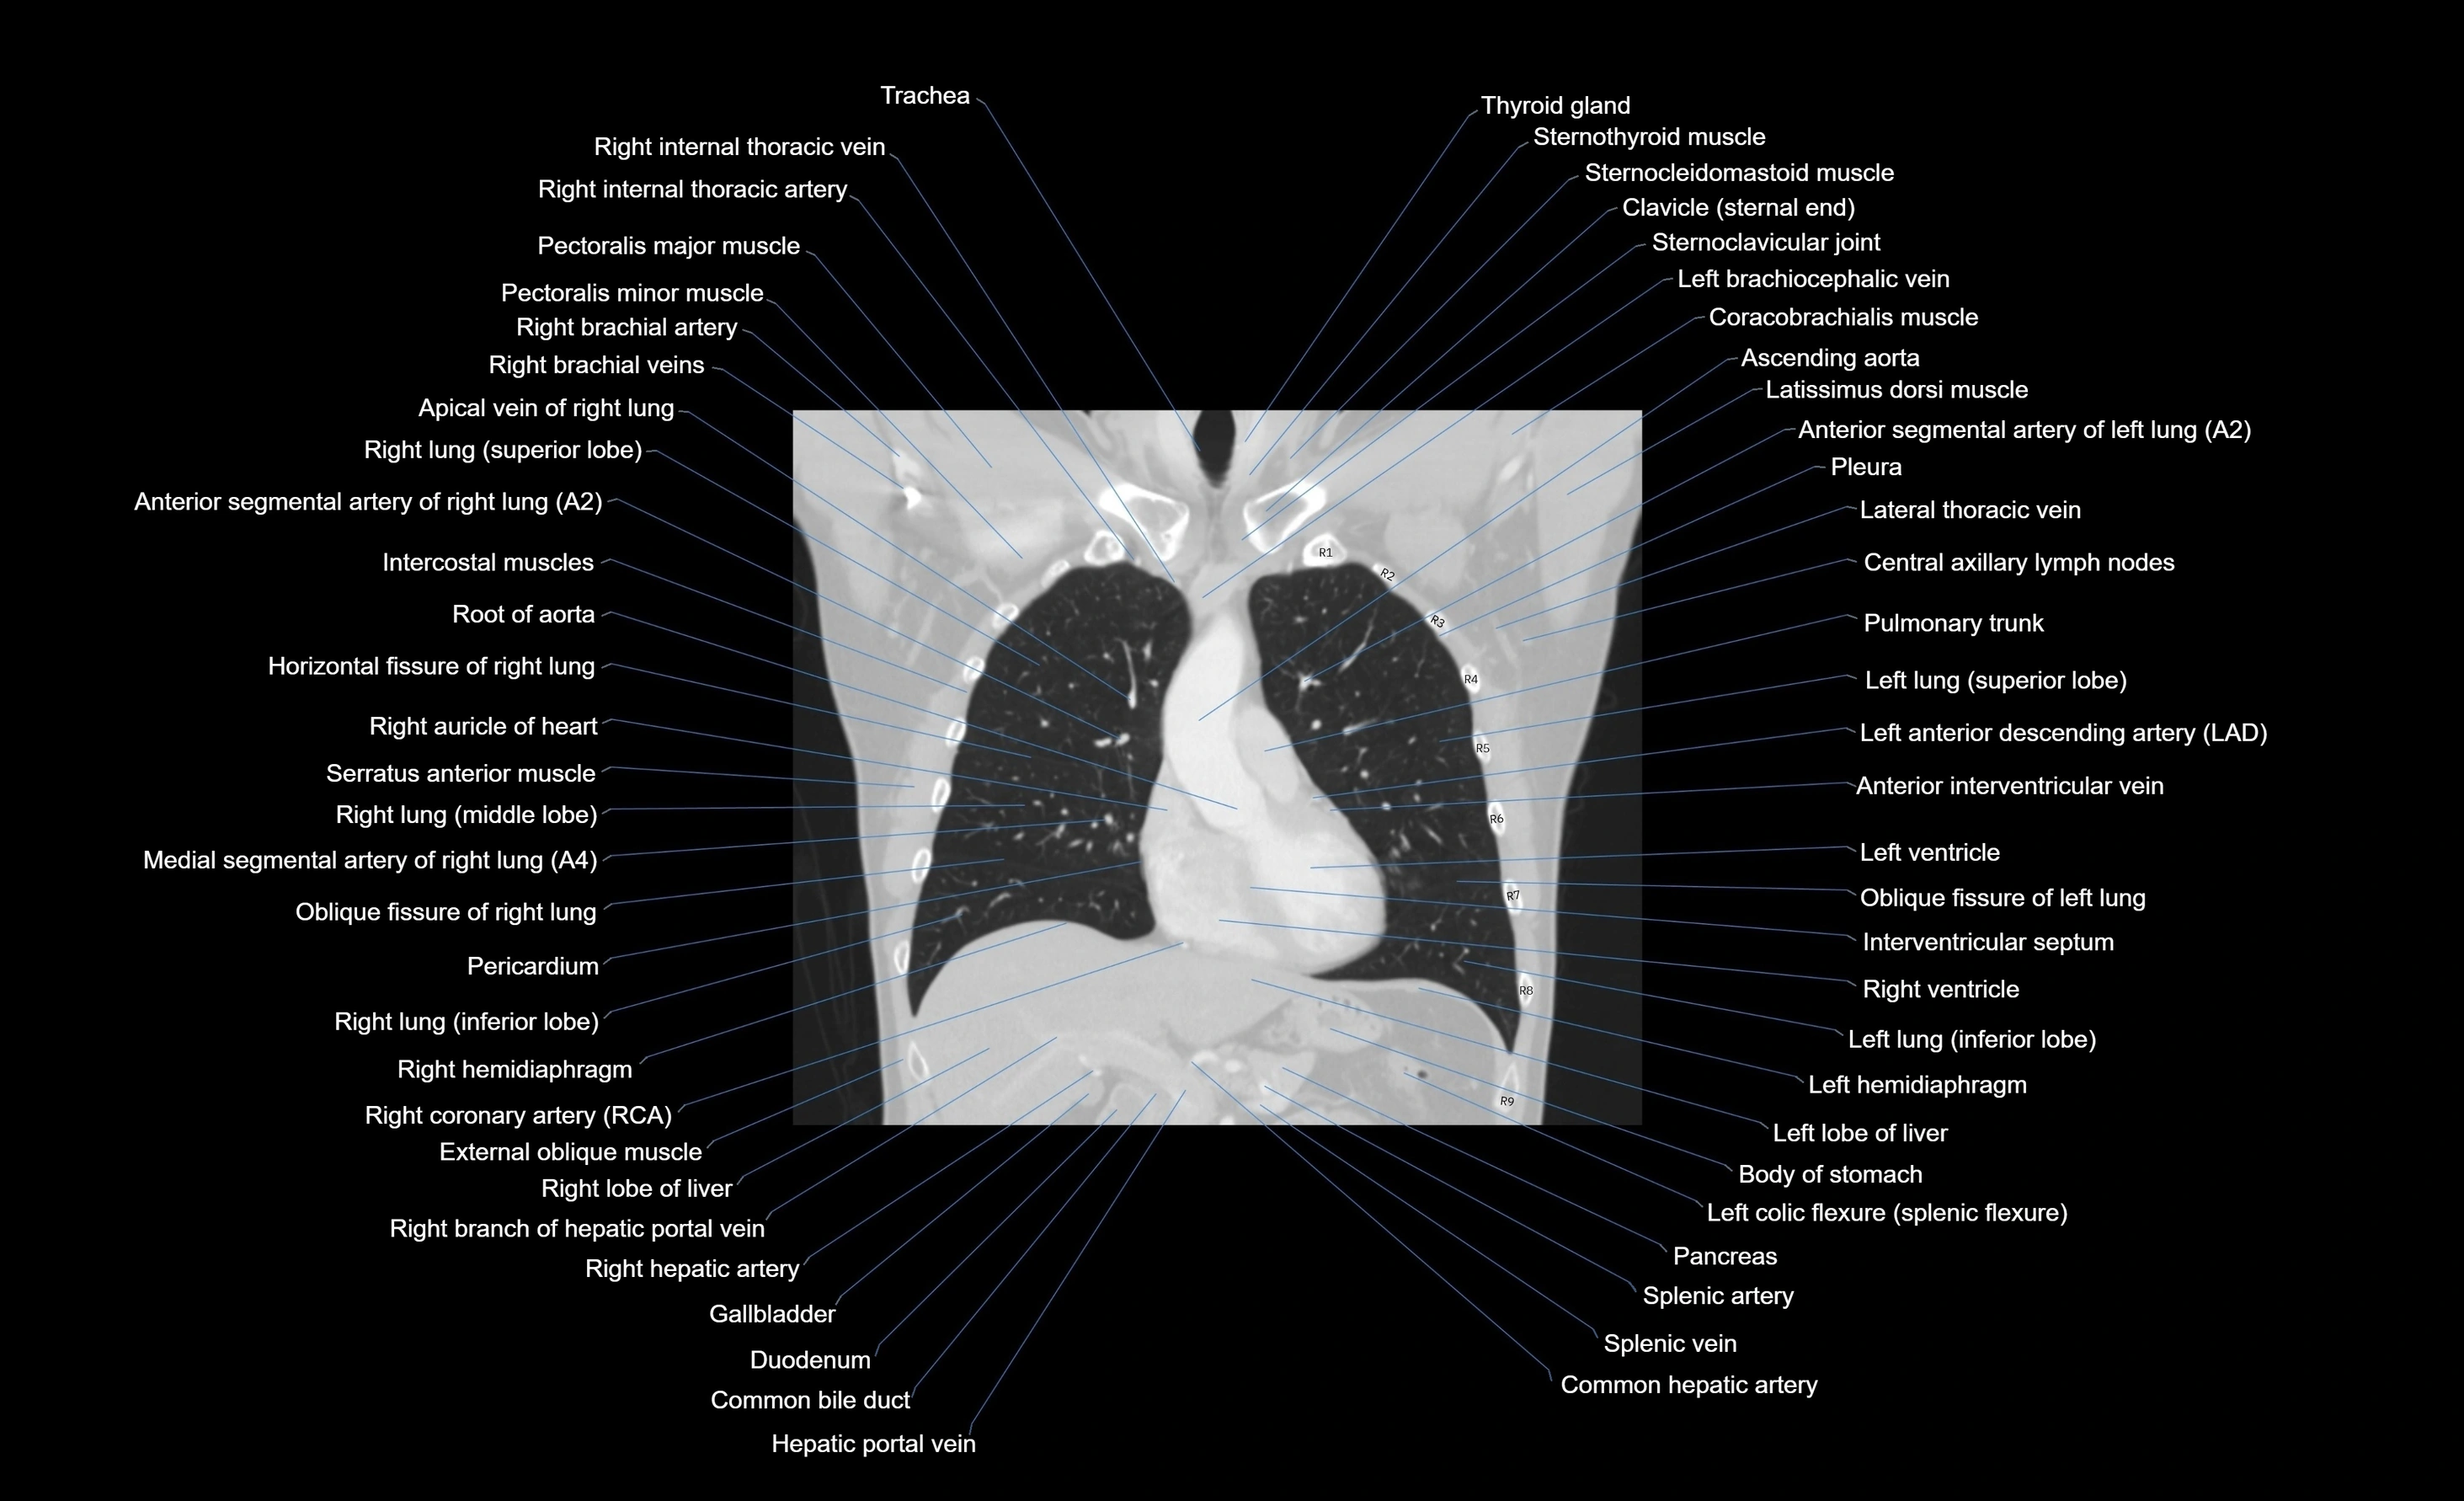

CT images